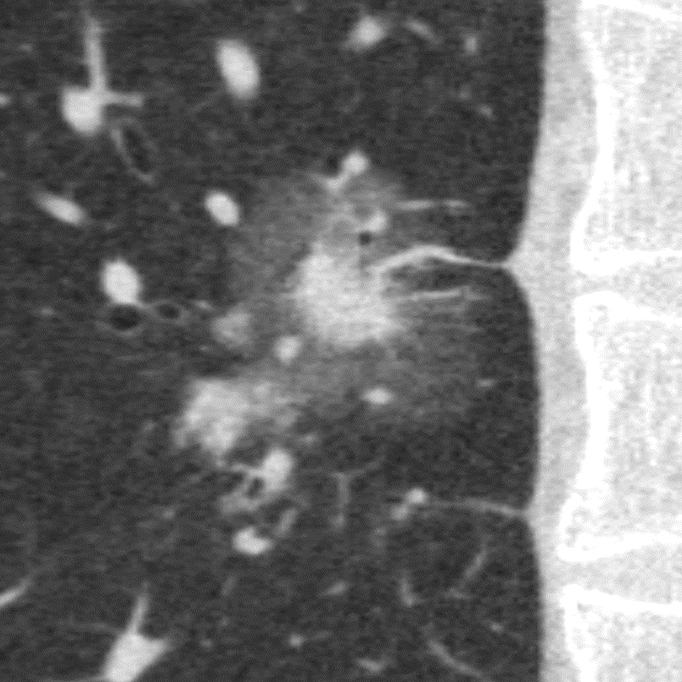

Порівняння звичайної роздільної здатності з ультрависокою роздільною здатністю (УРЗ)²

Звичайна КТ 0,5 мм